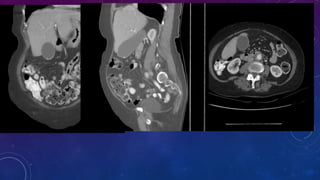

CHRONIC CALCIFIC PANCREATITIS

• #13 Chronic calcific pancreatitis